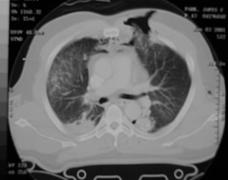

Contuzie pulmonara stanga Contuzie pulmonara dreapta

Contuzie pulmonara dreapta.Imagine CT